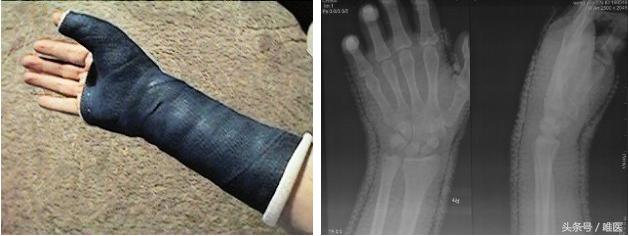

对于1-2周内的新鲜损伤,可采用闭合性手法复位,步骤同月骨周围脱位:在臂丛麻醉下使前臂肌肉松弛,沿纵轴牵引腕关节,并背伸腕关节,一手固定月骨掌侧,另一手由腕背侧向掌侧推压腕骨,并逐渐屈曲腕关节,即可达到复位。只是在2周时须将腕关节由屈曲位转为中立位固定,4周时将长臂石膏托更换为拇人字型石膏固定直至愈合。舟骨骨折必须固定可靠,且固定时间长,定期复查X线正侧位,以观察舟骨血运及愈合情况。

Arora R等认为对腕关节长期石膏,易导致腕关节退行性变,及发关节炎,关节僵直、影响活动等,且与Agergis有相同观点认为石膏固定早期难以提供牢固的固定,晚期易出现腕中关节不稳,腕塌陷,舟骨骨不连等并发症,故主张行手术治疗。